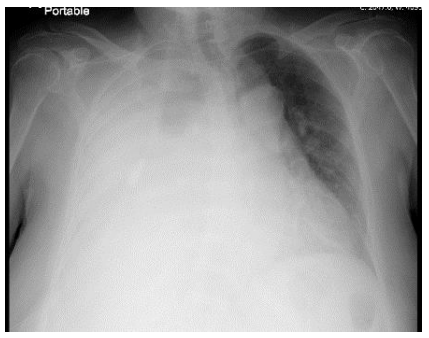

This is the case ofa 63 y/o female patient, with a past medical his. tory of adult polycystic kidney disease (ADPKD), hypertension, hypothyroidism, and hypercholesterolemia that was started on peritoneal dialysis one month ago. Patient presented to emer. gency department with shortness of breath and fatigue for the past 3 weeks that was getting worse, causing fatigue and ortho- pnea. Physical examination was remarkable for decreased breath sounds on the right side, no jugular venous distention, no pe- ripheral edema, and patent peritoneal dialysis tunneled catheter in the abdomen, Portable chest X-ray reported diffuse right White lung with mass-effect towards the left. The Chest CT scan with- out IV contrast reported large right-sided pleural fluid collection with near total collapse of the lung and polycystic kidney disease. Due to large amount pleural fluid, surgery services were consult- ed for chest tube placement, The analysis result of the pleural flu• id was consistent with transudate fluid and elevated glucose level (69 mg/dl), She had relief after chest tube drainage and no recur- rence of pleural effusion occurred after patient was switched to Findings suggest a pleuroperitoneal leak, due to given history of ADPKD with pleural effusion that occurs early after peritoneal dialysis initiation, and no other clinical findings of fluid overload